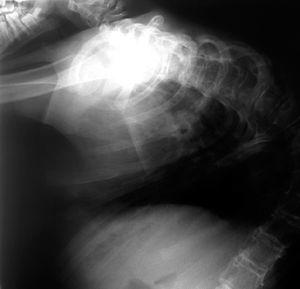

Ha presentado pielonefritis, gastroenteritis y neumonías de repetición, y numerosas crisis convulsivas tónicas (con puntas y polipunta-ondas generalizadas en el EEG). Por su cardiopatía presentó cianosis progresiva, con crisis hipoxémicas de frecuencia creciente y poliglobulia intensa (hematócrito 63,8 % en último control), que precisó en los últimos años oxigenoterapia domiciliaria. Asimismo, realiza rehabilitación por cifoescoliosis intensa (fig. 1). A pesar de todo, el niño ha mantenido siempre alimentación oral, administrada por otra persona, con un estado nutricional aceptable, una higiene escrupulosa corporal y bucodental, calendario vacunal correcto, y fisioterapia frecuente domiciliaria, con medidas ortopédicas posturales, que han permitido su transporte habitual y cierta autonomía hasta el final. No obstante, el retraso psicomotor era profundo, sin lenguaje ni manifestaciones emocionales, excepto la expresión o no de dolor, con hipertonía generalizada. A los 14 años y un mes presentó parada cardiorrespiratoria y muerte en el contexto de un proceso bronconeumónico.

Figura 1. Radiografía de tórax del enfermo, a la edad de 14 años.